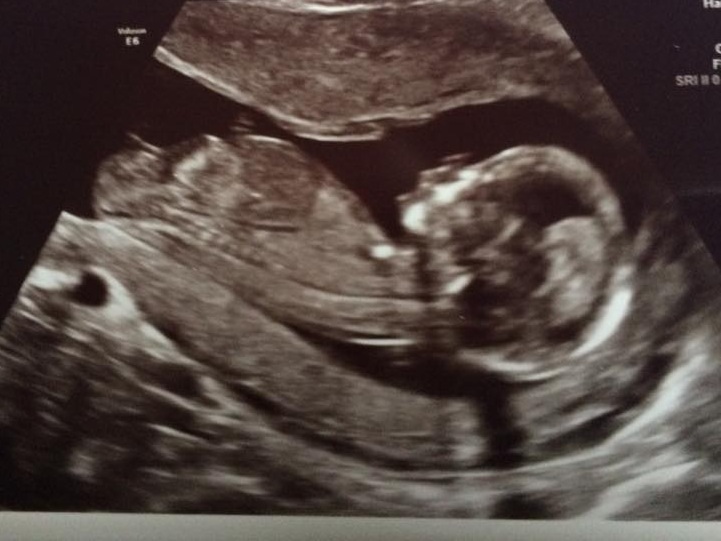

This scan was done last week at 13 weeks. Any guesses on gender please and thanks so much. :)

I would say girl but more based on skull theory. The nub has a significant end and baby is on a bit of a Lean so maybe boy??